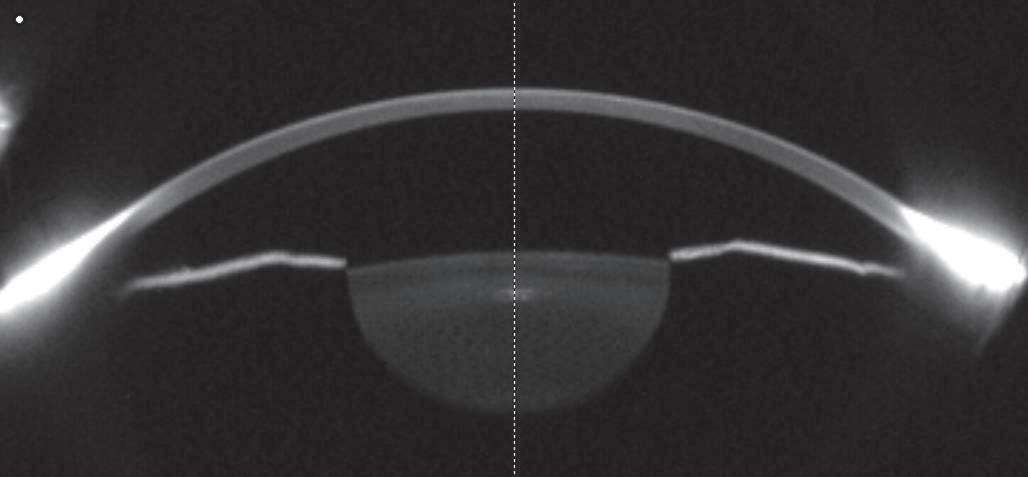

图3-7 正常人眼的Scheimpflug截面图。可显示角膜前表面、后表面、晶状体前表面、虹膜前表面。晶状体透明度、前房深度和前房角均能通过计算得出。